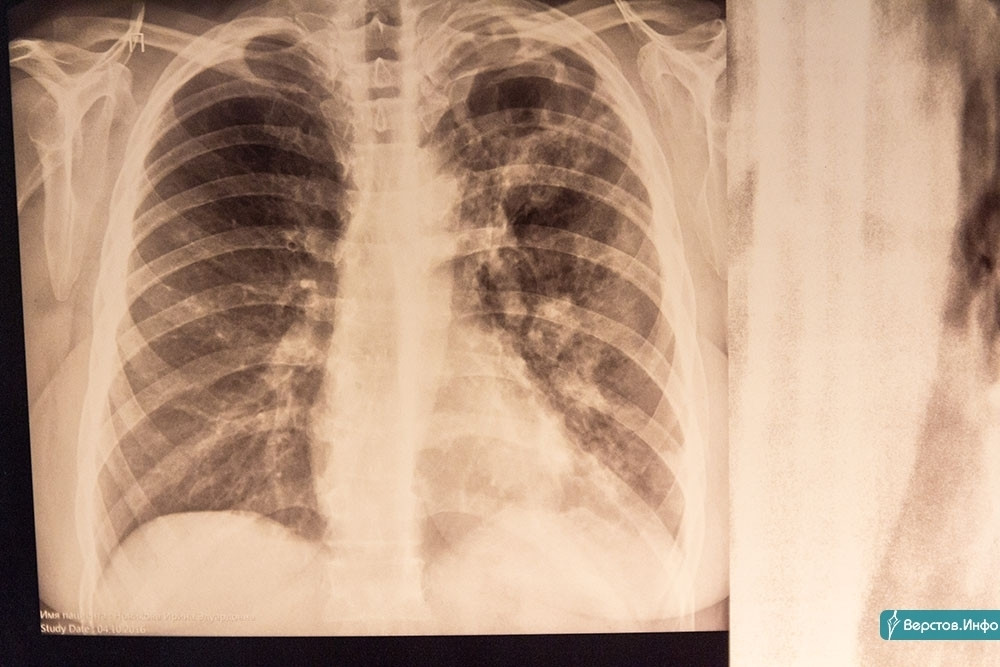

Игнорируют прививки и профосмотры! В Магнитогорске в 2021 году туберкулёз выявили у 167 горожан, 10 из них – дети

Каждый год во всем мире этим коварным и опасным заболеванием заражается около 10 млн человек, 1 млн – ежегодно погибают от туберкулеза. В России эпидемиологическая ситуация по туберкулезу каждый год остается стабильно напряженной.

По словам главврача ГБУЗ «Областная туберкулезная больница № 3» Анатолия Шалагина, в Магнитогорске эпидемиологическая ситуация имеет свою специфику. Высокая заболеваемость туберкулезом в нашем городе обусловлена значительным числом больных наркоманией в сочетании с ВИЧ-инфекцией. В 2021 году туберкулезом заболели 167 магнитогорцев, в том числе 10 детей и подростков. Среди вновь выявленных случаев заболевания в 40 % туберкулез сочетался с ВИЧ-инфекцией. И с каждым годом эта цифра неуклонно растет.

Наряду с этим отмечается ежегодное нарастание числа случаев туберкулеза с множественной лекарственной устойчивостью (МЛУ). В прошлом году каждый третий бацилловыделитель имел туберкулезную палочку, устойчивую к обычным противотуберкулезным препаратам. Причинами этого являются бесконтрольное применение населением антибиотиков и низкая санитарная культура горожан.

Основным методом профилактики туберкулеза является вакцинация, которая должна проводиться всем здоровым новорожденным в родильных домах. Однако ежегодно отмечается значительное число случаев, когда родители отказываются от вакцинации. В 2021 году прививки от туберкулеза получили лишь 89 % новорожденных детей. На сегодняшний день в Магнитогорске уже более 500 детей не имеют прививок от туберкулеза.

Наряду с вакцинопрофилактикой важное место занимает своевременность прохождения населением профилактических медицинских осмотров на туберкулез, которые имеют своей целью раннее выявление патологии. Чем раньше будет выявлено заболевание, тем быстрее оно будет вылечено полностью. Согласно действующим нормативно-правовым актам все жители города должны ежегодно проходить профилактический осмотр. Однако на практике значительная часть населения игнорирует профосмотры, надеясь, что туберкулез обойдет их стороной. Зачастую уже заболевшие люди своевременно не обращаются за медицинской помощью, в результате чего у них формируются тяжелые формы заболевания. При этом они заражают своих близких, соседей, коллег по работе… Важно знать и помнить, что сегодня туберкулезом может заразиться КАЖДЫЙ. Заражение может произойти везде.